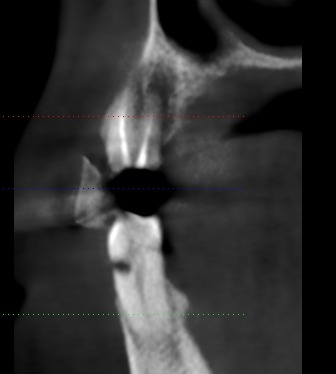

CASE BY DR. SMIJAL -- PRE OPERATIVE CBCT

3 mm width with unfavorable angulation.  In prosthetics angle abutment needed with tall and unaesthetic crown.